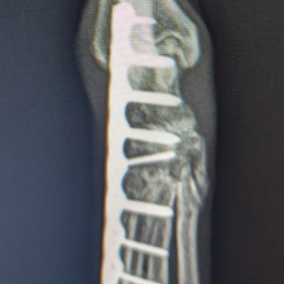

症例追加(2025/09/23)

HPの外科の「その他の整形外科疾患」のページに、犬の足根関節の部分関節固定術を追加致しました。(コチラ)足根関節は脛骨、腓骨、踵骨、距骨、足根骨、中足骨と複数の骨で形成され、その関節構造は複雑であり複数の靭帯と腱で安定化されています。足根関節の脱臼や亜脱臼は、主に落下や激しい運動中の外傷によって生じます。症状として、患部は熱感を持って腫れ、動物は痛みにより後肢を挙上したり、負重を避けるように行動します患部g腫れ、動物は痛みにより歩行時や排泄時に体重がかからないように庇。治療法は、軽症の場合は副子や装具による保存療法を行いますが、重症の場合は靭帯修復や関節を固定する関節固定術を行う必要があります。歩行異常や足を庇うような仕草が認められる場合はお早めにご相談下さい。

獣医師 臼井